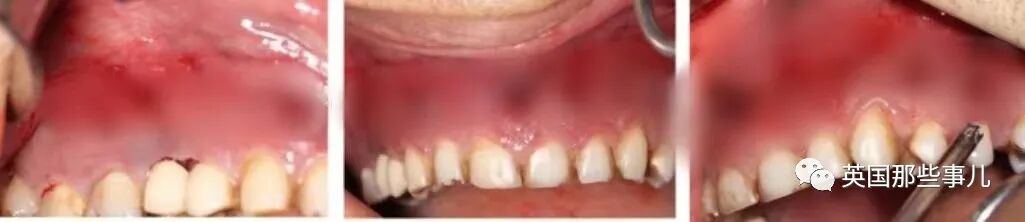

醫生打開他的頜面部後,發現他的牙齦感染嚴重,並擴散到口腔、鼻腔和下頜,下半張臉內部已經面目全非。

醫生切除掉他的壹塊頜骨,從上下牙床拔掉12顆牙齒,

還從他的兩側上頜竇部位清除掉黑色的壞死組織,下鼻甲部位的壞死也進行了切除。

(A:切除掉的部分頜骨,B:拔掉的牙齒)